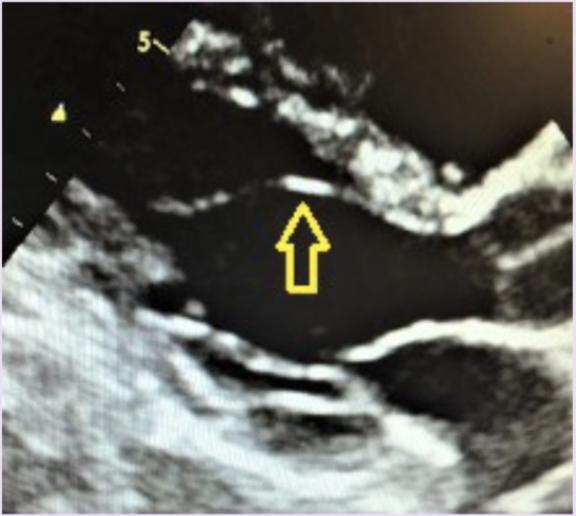

13

What is the arrow pointing to?

A

AMVL continuity